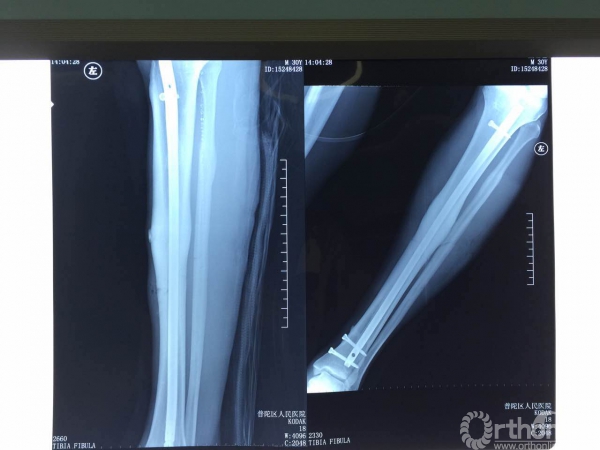

正常术前准备后,手术在透视下按计划顺利进行。术中扩髓11.5mm, 使用直径10mm、长度400mm髓内钉进行内固定。由于腓骨没有移位,腓骨切开固定后有可能延长胫骨愈合时间,基于这方面担心,专家团队决定不对腓骨进行固定。为将对肌肉的刺激降到最小,专家们使用近端螺钉埋头技术,接近完美的使钉头尽可能与皮质水平。

不顾X光射线对自身的影响,专家们术中反复透视,确定螺钉位置及长短,做到每根螺钉固定都恰到好处。手术顺利,完全按照专家团队预期计划进行,结果满意,术后石膏托固定。

X光片示:固定位置好,骨折线几乎看不到。